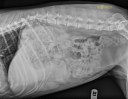

RadioQuiz 24 – Abdomen gonflé et tendu